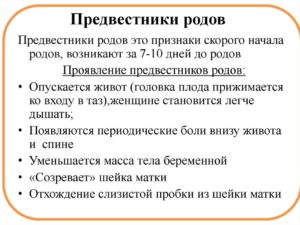

Даже повторнородящие женщины часто пропускают предвестники начинающихся родов, хотя, казалось бы, должны помнить, как начинается процесс появления малыша. Итак, на что следует обратить внимание:

- Перед родами у многих женщин снижается аппетит. Многие будущие мамы отмечают, что вес перед родами может стоять на месте или уменьшаться на несколько килограммов.

- На последних неделях женщина может ощущать тренировочные (ложные) схватки. Когда схватки становятся более ощутимыми, болезненными и продолжаются с регулярным интервалом, пора ехать в роддом. Выпейте таблетку но-шпы, постойте под теплым душем, полежите или посидите в расслабленном состоянии. Если болевые ощущения исчезли, вызывать бригаду скорой помощи рано.

- Перед родами обычно отходит пробка, которая представляет собой густую слизь, часто с примесью кровянистых прожилок. Если вы обнаружили кусочки пробки, это может послужить сигналом приближающихся родов. Но у некоторых женщин после отхождения пробки может пройти какое-то время, прежде чем начнутся роды.

- Часто в последние дни перед родами у будущих мам случается расстройство желудка.

Непосредственно перед родами в организме женщины происходит множество изменений: изменяется состояние связок, мышц, меняется гормональный фон, происходят психологические процессы, которые не могут оставаться незаметными. Это и есть предвестники приближающихся родов.

Предвестники родов в 39 недель у первородящих женщин могут отличаться от процессов, которые происходят в организме женщин, которые готовятся стать мамой в очередной раз.

Женщина, которая уже прошла в прошлом процесс родоразрешения, более внимательно прислушивается к своему организму.

Физиология повторнородящей женщины отличается тем, что мышцы влагалища и шейка матки менее упругие, а предвестники наступают позже, чем у женщины, которая готовится стать мамой впервые.

Достаточно часто повторные роды начинаются раньше, на 38-39 неделе, в то время, когда первородящие женщины могут ждать до 40-41 недели.

Предвестники родов на 39 неделе у повторнородящих могут быть такими:

- Отхождение слизистой пробки;

- Начало регулярных схваток;

- Опущение живота;

- Снижение веса.

Кроме объективных предвестников, выделяют также субъективные ощущения (нервозность, тревожность, бессонница, эффект гнездования). Но, почувствовав психологический дискомфорт, не стоит ехать в роддом, лучше дождаться достоверных предвестников начинающихся родов (отхождение околоплодных вод, регулярные схватки).

На 39 неделе беременности предвестники родов у первородящих несколько отличаются от симптомов, которые могут наблюдаться у женщин, вынашивающих второго ребенка. Специалисты выделяют такие основные предвестники родов на 39 неделе беременности, которые могут проявляться за неделю до начала родовой деятельности:

- Отхождение слизистой пробки, что выражается увеличением слизи в выделениях.

- Опущение матки, на фоне чего становится легче дышать.

- Снижение массы тела и отсутствие аппетита.

- Учащение ложных позывов к дефекации.

Предвестники родов у повторнородящих отличаются своей скоротечностью. То есть, после появления определенных симптомов, роды могут начаться практически сразу. Быстротечные роды могут представлять угрозу для ребенка. Поэтому, когда тридцать девятый недельный период беременности у повторнородящих женщин связан с тем, что болит живот и тянет поясницу, то лучше сразу обратится в роддом.

Предвестники родов у повторнородящих и первородящих женщин всегда сопровождаются учащением ложных схваток. При этом сильно болит поясница и тянет живот. Если такие симптомы появились, то нужно ожидать начало родов в ближайшее время, а это значит, что необходимо срочно отправляться в роддом.

Наиболее распространёнными предвестниками родов на 39 неделе являются:

- слабые тянущие боли в нижней части живота (тренировочные схватки);

- отхождение слизистой пробки — едва заметные кровянистые выделения из половых путей;

- из сосков может увеличиться количество выделений молозива;

- наблюдается некоторое снижение веса, при этом аппетит будет повышен;

- учащенные позывы к мочеиспусканию и диарея – это еще один из «симптомов» скорого наступления родов;

- появление бессонницы или же наоборот, сонливости;

- наблюдаться боли в пояснице;

- опускание живота и выпячивание пупка. Обычно после этого будущей маме становится гораздо легче дышать;

- снижение веса от 1 кг до 1,5. Такое «похудение» обусловлено уменьшением отечности.

Заметное невооруженным глазом для акушера изменение в организме женщины, которое она не ощущает — это размягчение шейки матки. К 39-ой неделе беременности шейка матки приоткрывается, готовясь к детородному процессу.